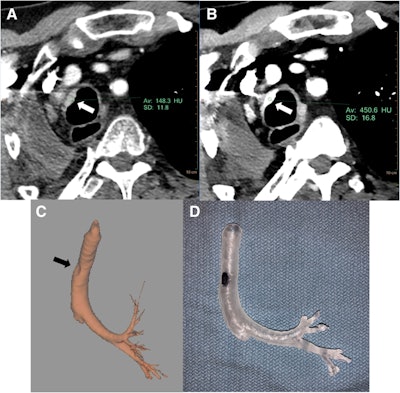

Conventional CT scan (A), DECT scan (B), 3D volume-rendered DECT scan (C), and 3D-printed model of the bronchial tree (D). The virtual monoenergetic image of the DECT scan enhances visualization of the tracheal malignancy (white arrow). Image courtesy of Kikano et al. Shared via Creative Commons license.Using virtual monoenergetic images of the DECT scans in place of conventional CT offered several advantages, including the following:

- More than doubling the attenuation of vasculature and other key structures

- Decreasing segmentation time

- Enhancing fracture visualization

- Reducing metal artifacts by as much as 90%